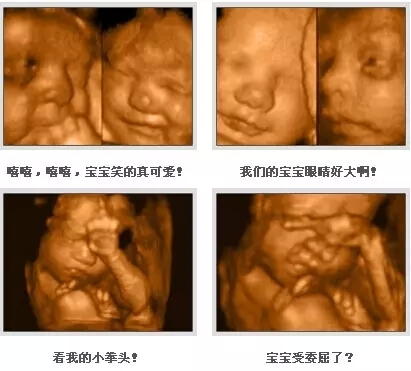

四維彩超能夠全方位、多角度的觀察宮內(nèi)胎兒的生長發(fā)育情況,如胎兒孕周、大小,還可排查胎兒先天畸形疾病。如唇腭裂、無腦兒、腦脊膜膨出、臍部腸膨出、腸道閉鎖、尿道梗阻、短肢畸形、四心腔、羊水過多、過少等。四維彩超對于優(yōu)生極其關(guān)鍵,可不少孕媽會遇到一種尷尬的情況,也讓B超醫(yī)生很頭疼,那便是胎寶寶老趴著,基本上看不到五官及表情。

胎寶寶在媽媽的子宮內(nèi)喜歡腹部朝內(nèi),背部朝外的蜷曲姿勢,這種姿勢是最自然的自我保護(hù)姿勢,既有安全感,還有利于寶寶的神經(jīng)系統(tǒng)發(fā)育??蛇@樣便排除不了面部的畸形,也滿足不了孕媽想要目睹寶寶真顏的好奇心。